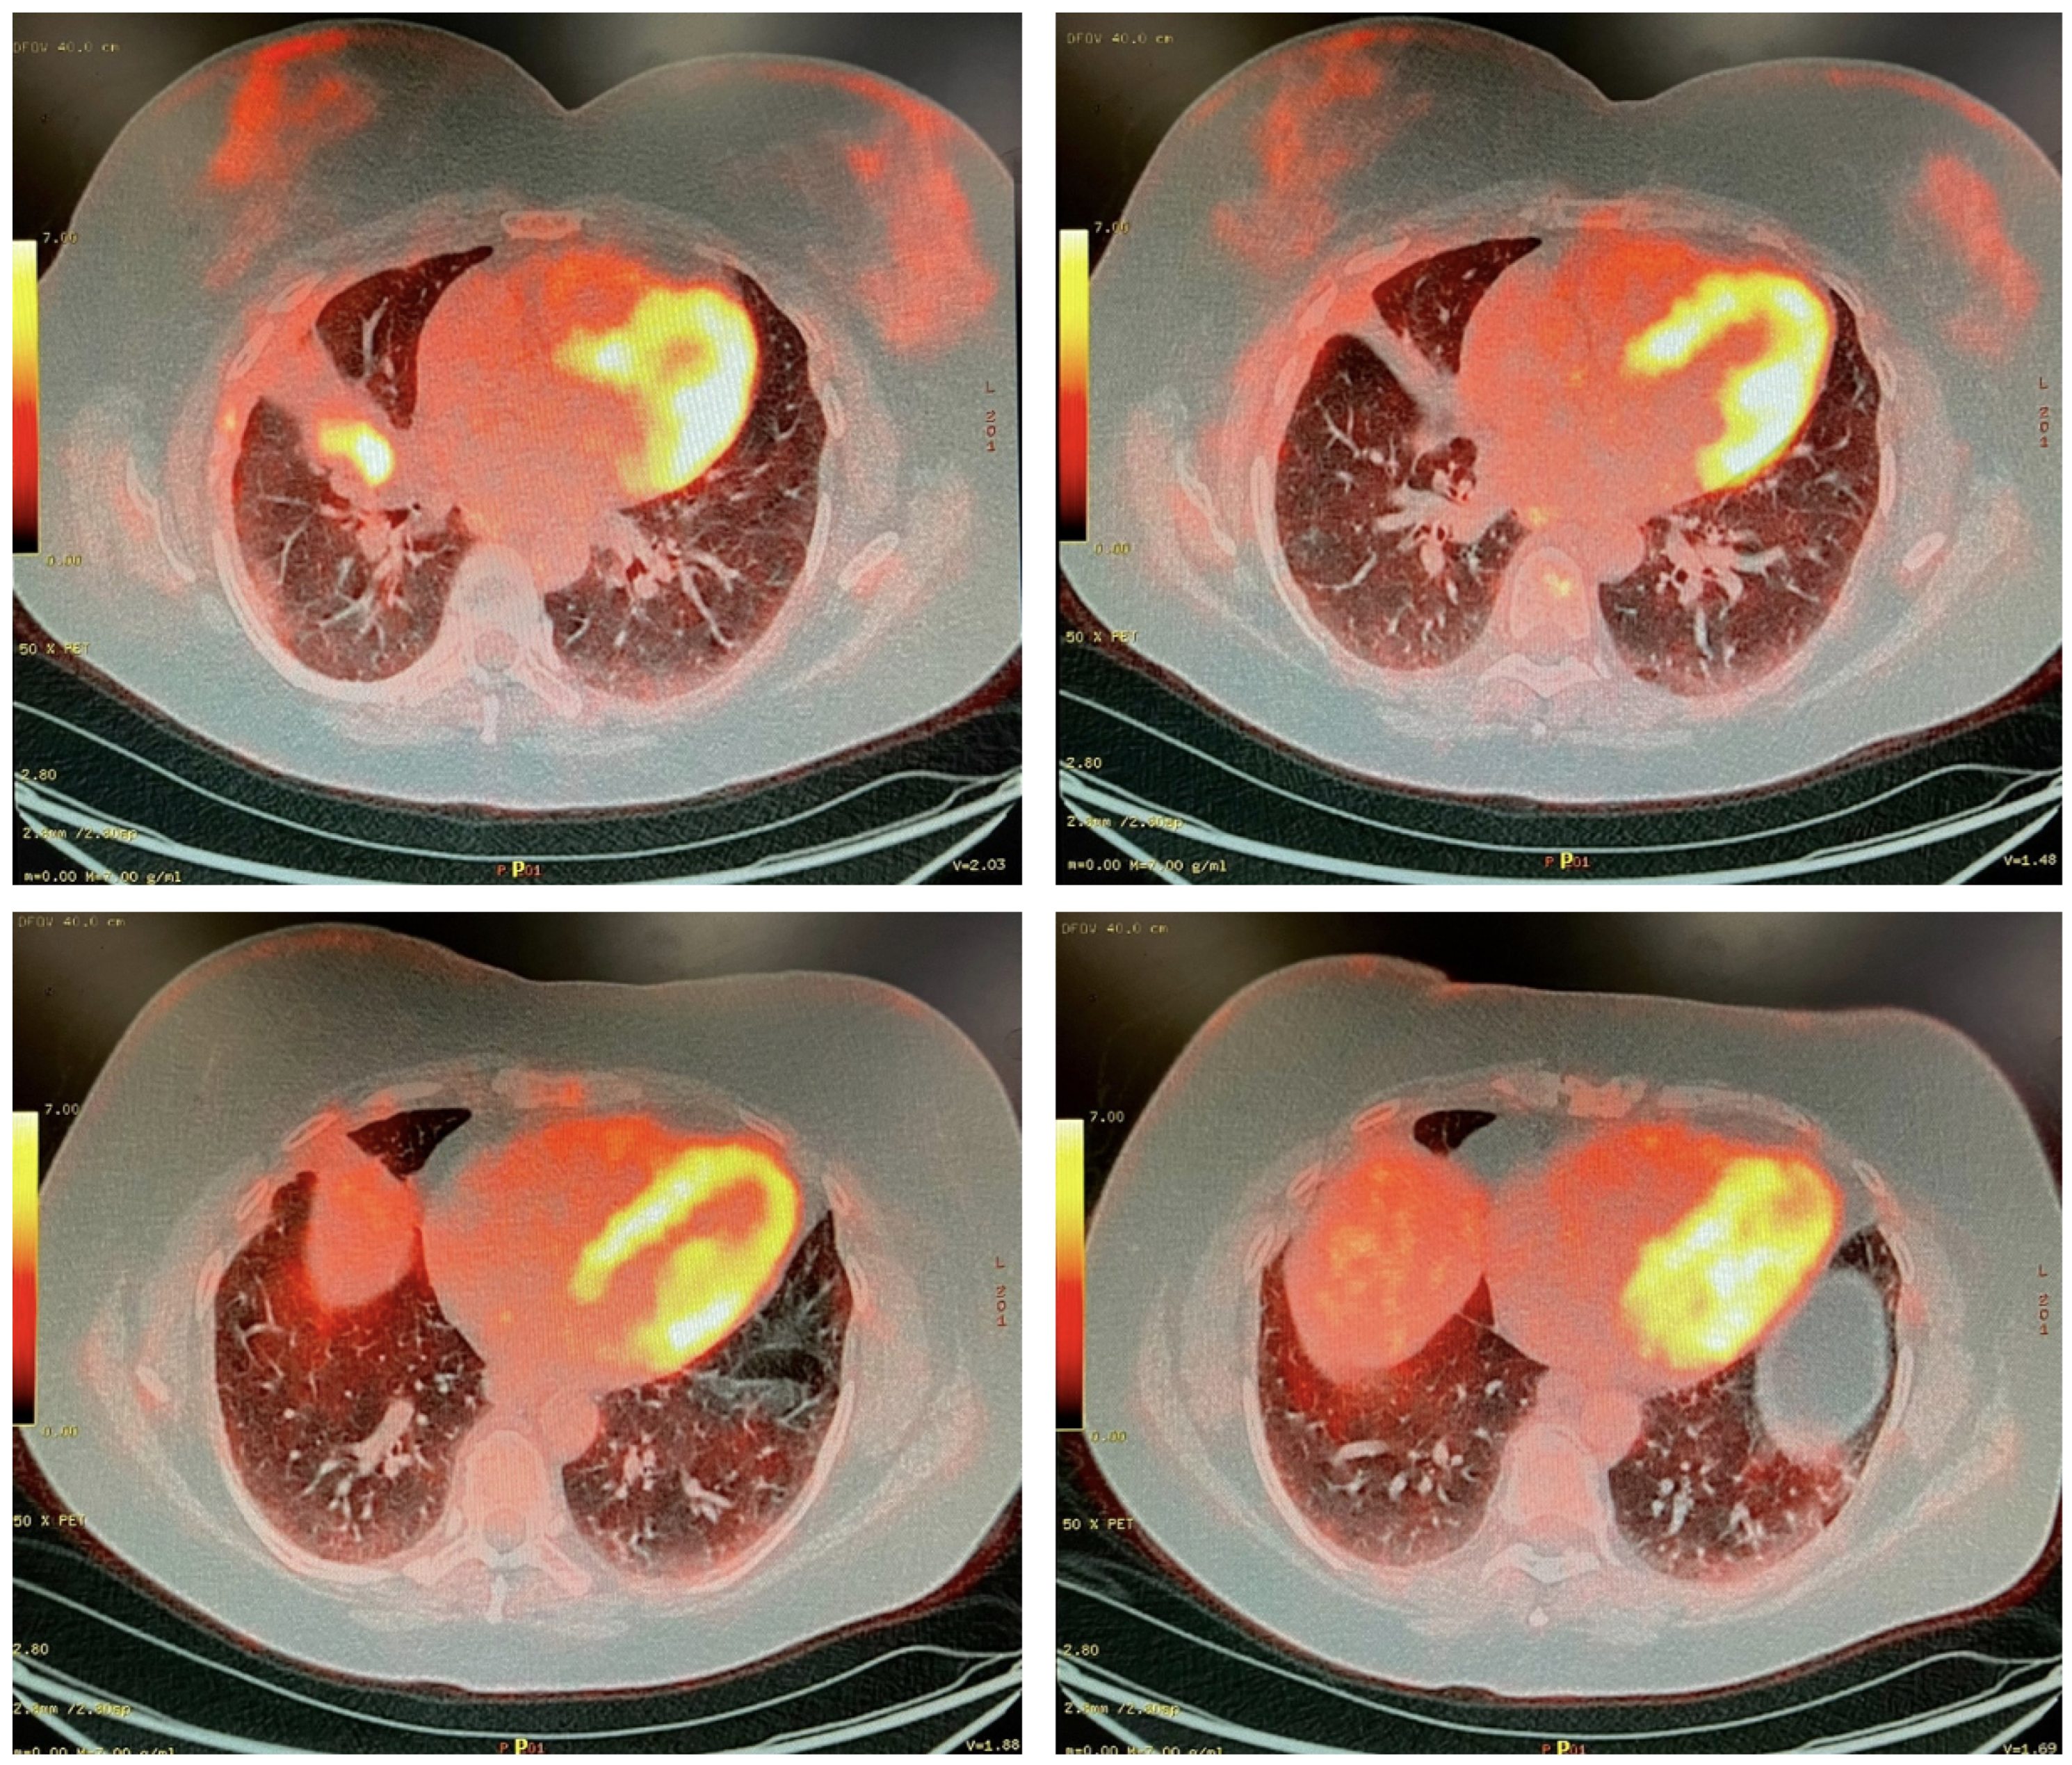

A 53-year-old women with no history of tobacco use presented with cough and dyspnea during the autumn of 2016. A chest X-ray on 17 February 2017 showed a well-circumscribed spiculated right middle lobe (RML) lung mass adjacent to the right hilum. Follow-up CT on 1 March 2017 confirmed a 4.5 cm × 3.1 cm spiculated RML lesion, which was abutting and crossed the major fissure, bilateral mediastinal lymphadenopathy, and satellite nodules throughout the right lung, as shown in Figure 1. A positron emission tomography (PET) CT on 31 March 2017 showed intense fludeoxyglucose-18 (FDG) avidity of the RML mass with an SUV max of 20.5, in addition to FDG avid right hilar, subcarinal, paratracheal, and extrathoracic right subclavicular lymph nodes (Figure 2). Finally, there was an FDG avid pleural-based nodular density noted in the low anterior right costophrenic angle region (M1a).

Figure 1. (a) Computed tomography revealing a 4.5 × 3.1 cm opacity in the right middle lobe lung adjacent to the right hilum. (b) Positron emission tomography (PET) slice uptake corresponding to the abnormal fludeoxyglucose (FDG) enhancement in a right-sided extrathoracic subclavicular lymph node at the T3 level. (c) PET scan slice showing FDG uptake in mediastinal lymph nodes. (d) PET scan slice showing FDG uptake in a pleural-based nodular density in the low anterior right costophrenic angle region.